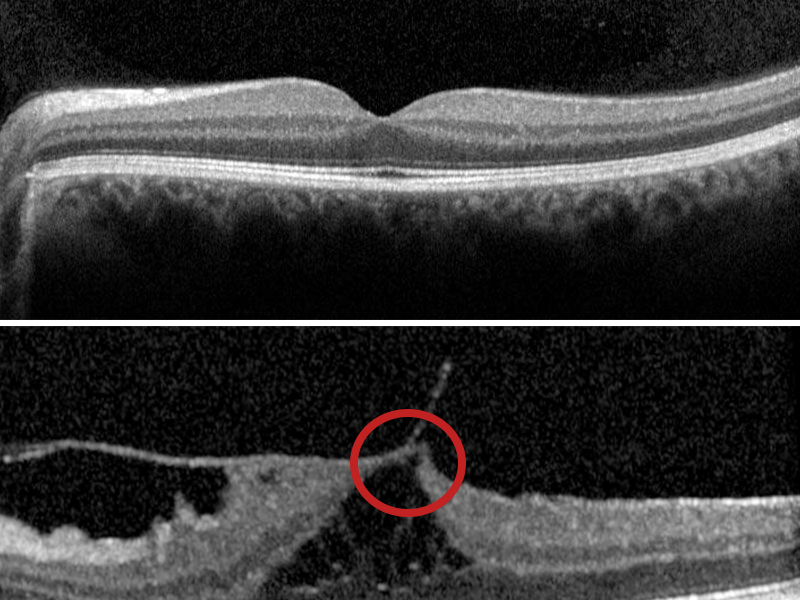

If the vitreous doesn’t fully separate from the retina, the remaining partially attached vitreous can pull and distort the macula. This is vitreomacular traction. In some cases, vitreomacular traction can progress and form a macular hole.

Your eye health professional may also use optical coherence tomography (OCT) to confirm the extent of your condition. OCT is a non-invasive scan of the tissue layers of the retina.